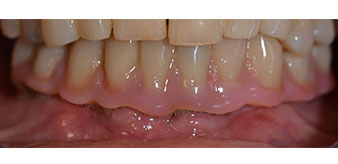

Successivamente, sono state prese le impronte e il morso di costruzione della paziente, per consentire al tecnico dentale di iniziare a realizzare la ricostruzione provvisoria. Quest'ultima è stata innestata lo stesso giorno (Fig. 17 e 18).

Una volta trascorso il tempo necessario per la osteointegrazione, è stato possibile prendere l'impronta definitiva degli impianti e, poi, è stata realizzata la protesi definitiva (Fig. 19 e 20). A questo punto, il dentista e la paziente hanno potuto decidere insieme se utilizzare delle faccette in ceramica o in vernice acrilica, con una struttura in zirconio o metallo. In questo caso, il Dott. Pascu e il suo team hanno preferito delle faccette in vernice acrilica, a seguito della prognosi difficile sulla dentatura mascellare e sulla posizione allungata del dente 24. Questo tipo di faccette è solitamente molto più facile da adattare e, di conseguenza, può essere modificato per rispondere alla nuova situazione della mascella.